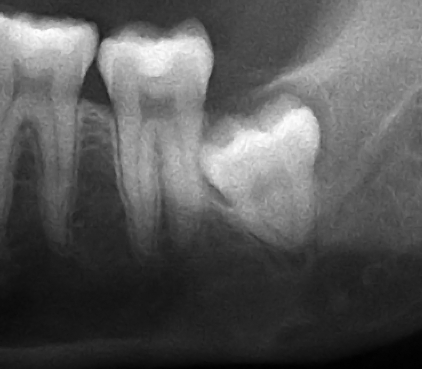

참고로 한 부위만 촬영하는

이 촬영에서 발생하는 방사선 노출량은 1회에 0.003mXv

매복된 사랑니 발치할 때 쓰이는 CT의 방사선 노출량은 1회에 0.09mSv